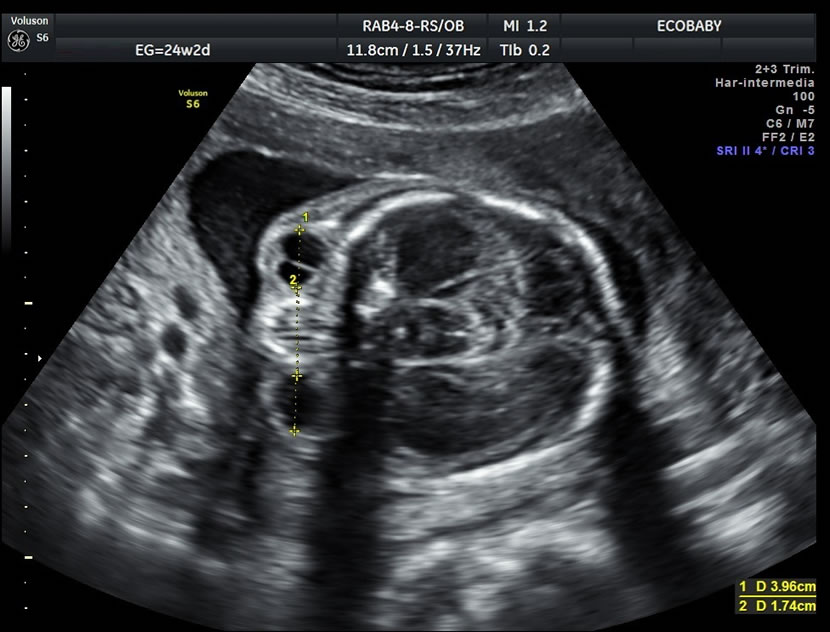

Cerebro, cuello, cara, tórax, corazón (diferentes cortes que muestran las cavidades y la correcta entrada y salida de arterias y venas), abdomen (normalidad de la pared, estómago, intestino, riñones, vejiga), miembros inferiores y superiores y columna vertebral.